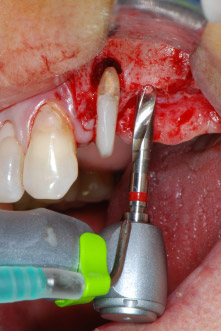

Un mese più tardi, nel giorno programmato per l'intervento, il dolore e l'infiammazione in corrispondenza del dente 24 erano minimi, ma era ancora presente mobilità di classe 2 secondo Miller. Dopo l'apertura dei lembi e la pulizia del tessuto periapicale e periradicolare infetto, l'estensione della mancanza ossea si è resa evidente (Figg. 2 e 3).

Si è mantenuta , tuttavia, l'idea iniziale di conservare entrambi i denti come appoggi temporanei del ponte durante il periodo di sei mesi per l'osteointegrazione degli impianti. In seguito la situazione si sarebbe assestata. In primo luogo, in un tentativo di risolvere il problema entro-periodontale, la superficie radicolare rimanente è stata attentamente sbrigliata con apparecchiatura piezoelettrica (Piezomed di W&H con l'attacco S1 a spatola, progettato in origine per l'erosione della parete laterale del seno mascellare) Fig. 4).